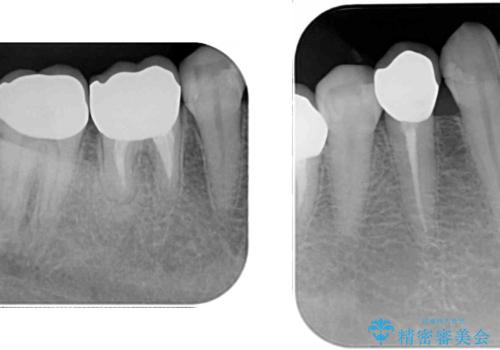

歯を削る量は増えますが、より長い期間再治療なく使用していただくことを最優先に考え、フルカバレッジのオールセラミックブリッジにて補綴することとしました。

他にも、奥歯の銀歯の下にもむし歯が多くあり、痛みが生じていたため、根管治療などを行った上で、オールセラミッククラウンにて補綴治療することとしました。

我々としては、治療により状態が悪化することだけは避けたいと考えているため、歯全体を覆うクラウンにすることで、より長持ちする治療を提供いたしました。